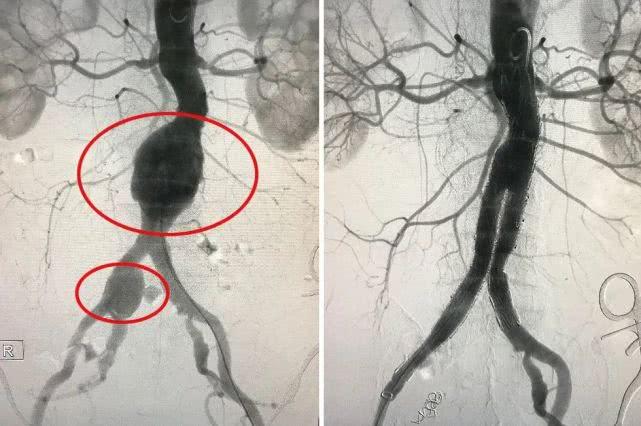

图左为术前,可见腹主动脉瘤和右侧髂总动脉瘤;图右为术后,腹主动脉,髂